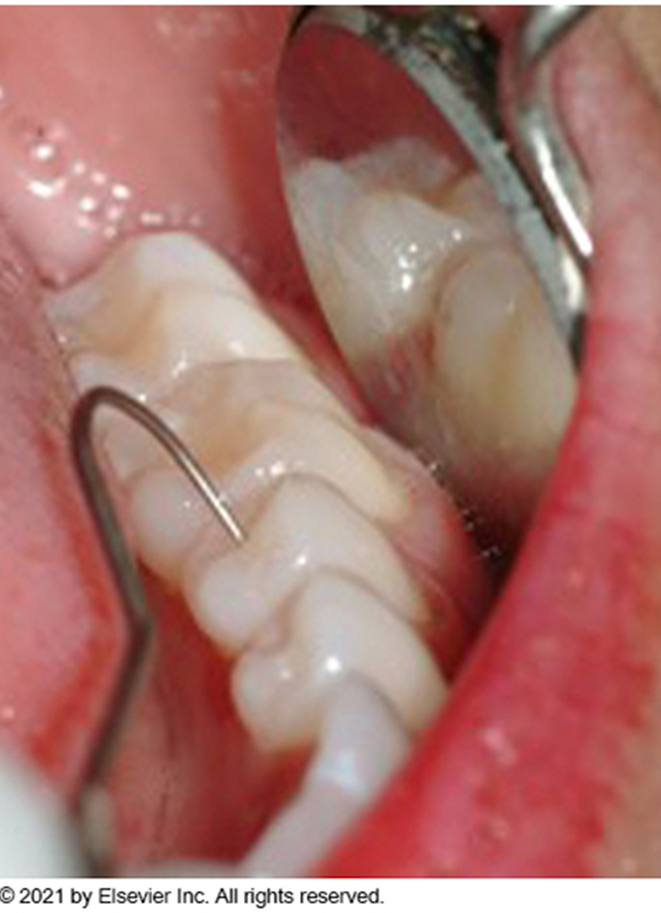

Instrumentation

The use of instruments to examine the teeth and surrounding tissues

Type of instruments commonly utilized to examine the teeth: Mouth mirror and explorer

Type of instrument used to examine the gingival tissues: Periodontal probe

Detection: Dentist uses an explorer to detect imperfections in tooth surfaces

Probing: Dentist or dental hygienist uses the periodontal probe to assess the gingiva for the presence of periodontal pockets